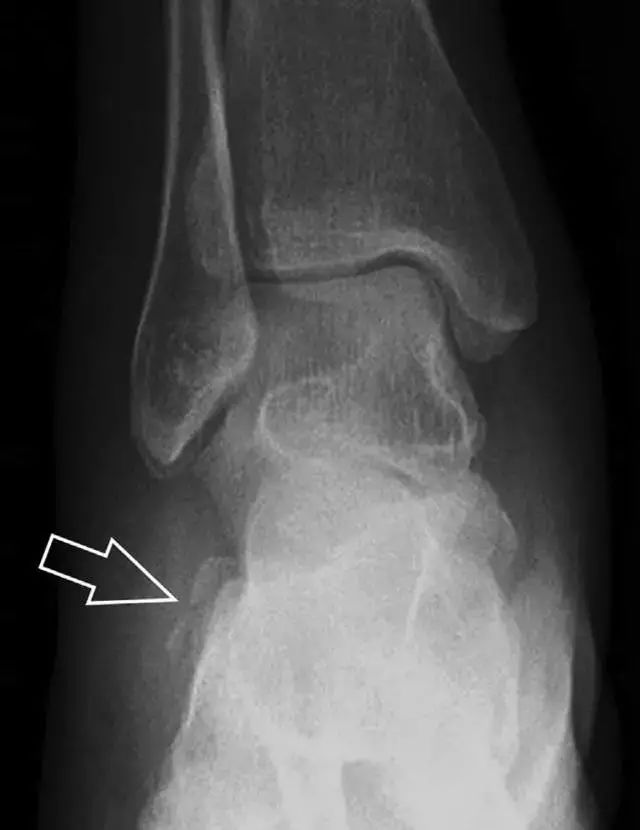

16胫骨后踝骨折

涉及到三角韧带和外侧副韧带(LCL)的复杂性骨折常常不难发现,尤其是存在表面软组织肿胀时。然而,后胫腓韧带牵拉引起的胫骨后踝骨折则很难发现。这些骨折大小不一(图 2),却很重要,因为他们常与胫骨远端螺旋骨折有关,或者是三踝骨折的一部分。

图 2 胫骨后踝骨折。A 侧位片示来源于胫骨后踝的一个小骨折碎片(箭头),因踝部扭伤导致B 另一位跖屈损伤的患者,侧位片示一个大骨折块(箭头)